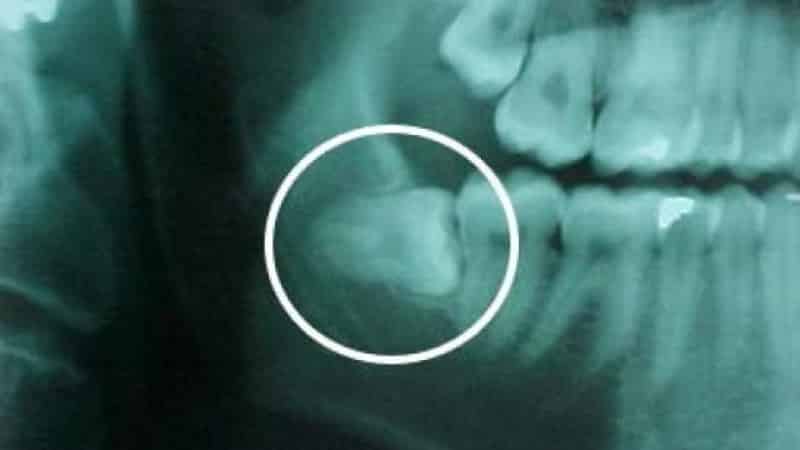

Как бороться с патологией

Регулярные посещения стоматолога необходимы для предотвращения побочных эффектов. Когда зуб мудрости растет неправильно, его обычно удаляют, чтобы избежать осложнений и вреда, которые могут быть причинены процессом прорезывания. Патологически сформированные моляры не выполняют свою функцию в процессе дробления пищи и часто вызывают воспаление и прикусывание слизистой щек или языка. Кроме того, повреждение слизистой ротовой полости может привести к инфекциям, грибкам, вирусам и бактериям. При консультации у стоматолога проводится рентгенография зуба для определения его особенностей и степени сложности. В некоторых случаях удаление зуба мудрости может быть сложной процедурой из-за анатомических дефектов челюсти. Пациентам рекомендуется отказаться от физических и эмоциональных нагрузок перед операцией, а также избегать горячих ванн, курения и употребления алкоголя. Операция начинается с местного обезболивания, после чего врач делает разрез десны и обрабатывает твердые ткани вокруг корней зуба. Рана закрывается швами после обработки противовоспалительным и антисептическим раствором. Продолжительность операции зависит от сложности случая и может занимать от полутора часов до нескольких часов. Стоматологическое долото, которое ранее использовалось для ампутации зуба мудрости, сейчас считается устаревшим и травмоопасным инструментом, который вызывает физический и психологический дискомфорт у пациента.